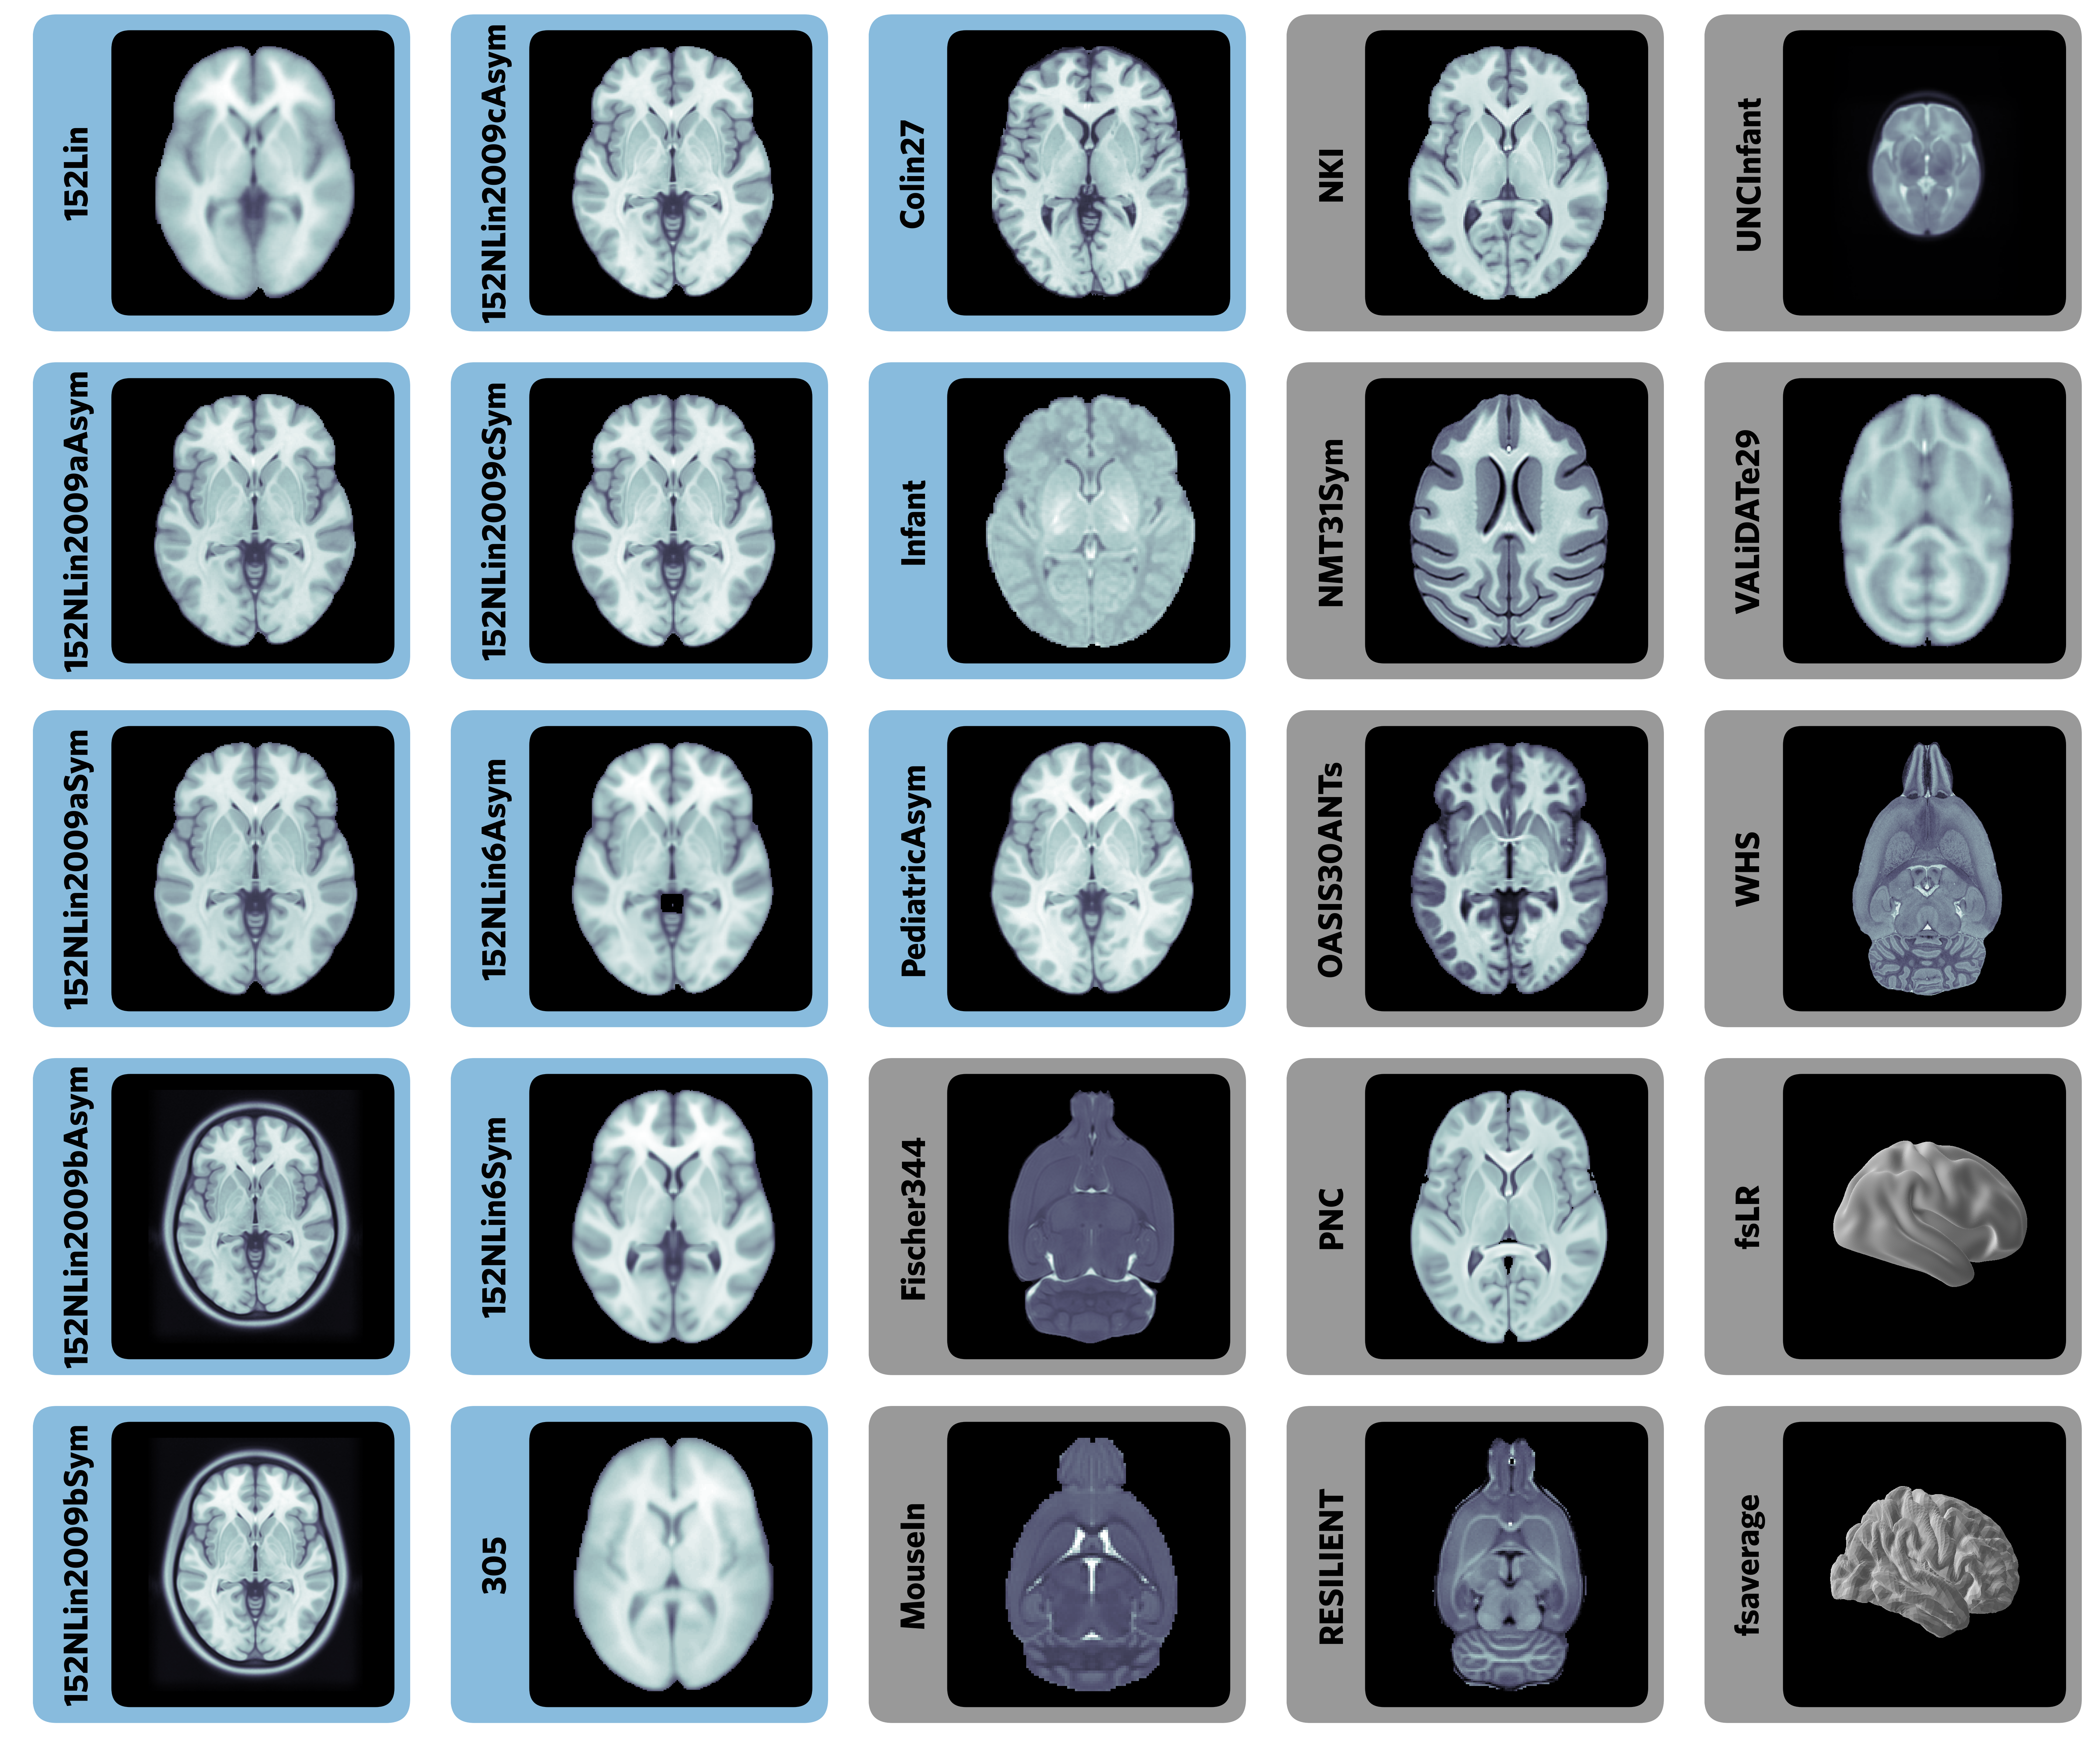

Templates and atlases are commonly used in neuroimaging research

There is significant lack of clarity in the use of these templates

Templateflow provides programmatic access to a database of templates and mappings between them

Easy to use for humans and machines:

Ciric et al., 2022, Nature Methods